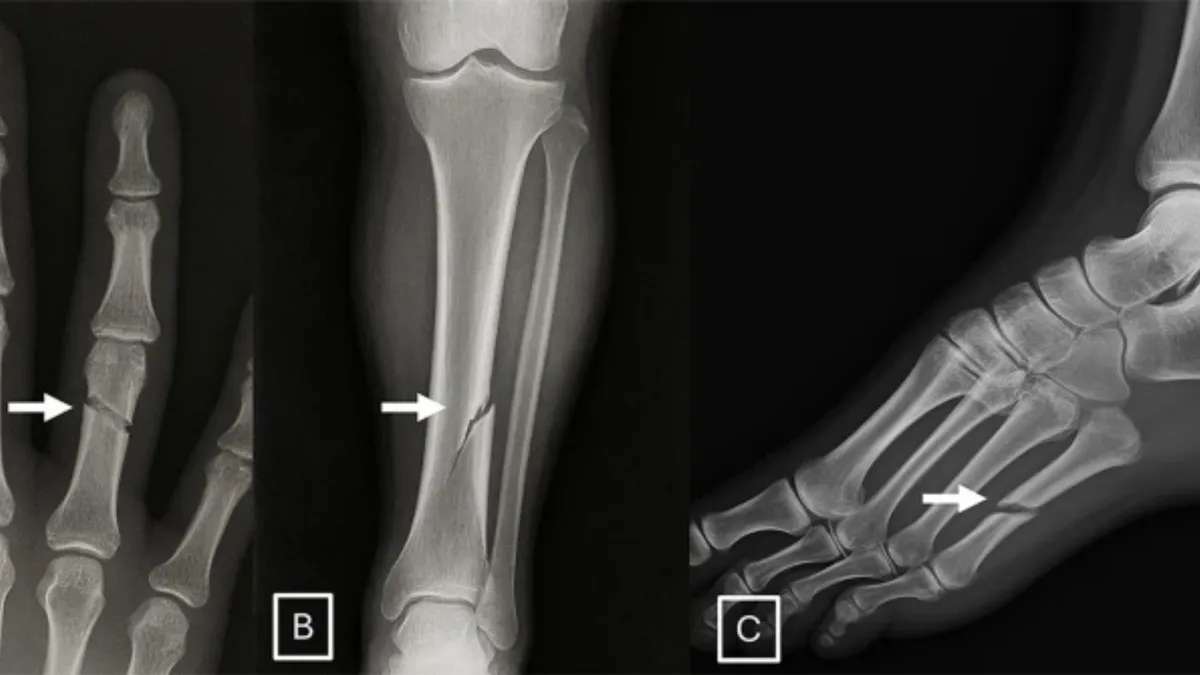

AI poate genera radiologii false (sursa: Radiological Society of North America)

Un studiu recent atrage atenția asupra unui risc major din domeniul medical: imagini radiologice false, generate de inteligența artificială, pot păcăli inclusiv radiologi experimentați.

Cercetarea, citată de revista Nature, evidențiază vulnerabilitățile serioase pe care această tehnologie le introduce în sistemele de diagnostic.

De exemplu, o fractură generată artificial ar putea deveni imposibil de diferențiat de una reală, ceea ce ar putea influența procese legale sau decizii medicale critice.